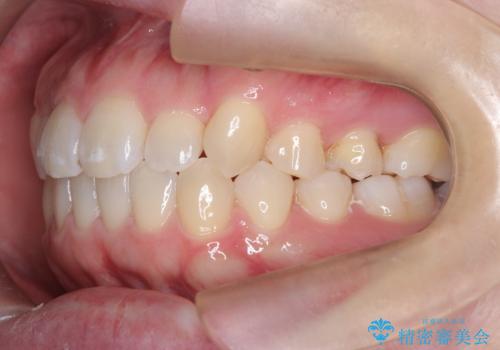

- 患者様は歯並びの乱れを気にされて来院されました。特に小臼歯の捻転(ねじれ)が強く、見た目だけでなく噛み合わせにも影響がありました。できるだけ目立たない方法を希望されていたため、インビザライン(マウスピース矯正)を基本としつつ、より精密な動きが必要な部分にはワイヤー矯正を併用する計画を立てました。また、小臼歯の捻転については**部分矯正(MTM:Minor Tooth Movement)**を取り入れ、効率的に改善を目指しました。

まず、全体の歯並びを整えるためにインビザラインを使用し、徐々に理想的な位置へと歯を移動させました。一方で、ねじれの強い小臼歯に対しては、**部分的なワイヤー矯正(MTM)**を行い、より精密なコントロールを実施。約2年の治療期間を経て、歯並びと噛み合わせが整い、見た目の美しさだけでなく、機能的な改善も達成しました。患者様からは「自然な仕上がりで、自信を持って笑えるようになった」と喜びの声をいただきました。